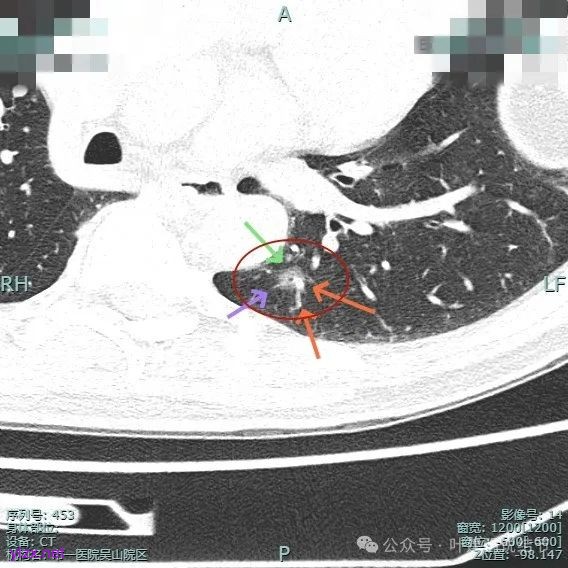

主病灶混合密度,血管进入;次病灶小且淡,但轮廓清。

血管进入扭曲,毛刺明显,整体轮廓清,灶内小空泡征。

主病灶血管进入,灶内空泡,表面浅分叶,整体轮廓较清。

上图蓝色箭头所指的是医用定位胶,天蓝色箭头是次病灶,红色箭头是主病灶,设计的切除线如虚线所示。我们打算进胸后确定定位胶所在平面,因为包括两处病灶均在同一平面上,然后我们游离下肺韧带,将后基底段此部分肺组织向下解剖游离开,直到下肺静脉下缘,并贴着下叶静脉边缘往肺实质深面用切割缝合器切开并闭合肺切缘,按CT上大概距离推算,到越过次病灶深度后转向胸肋面,切除该范围内的肺组织。